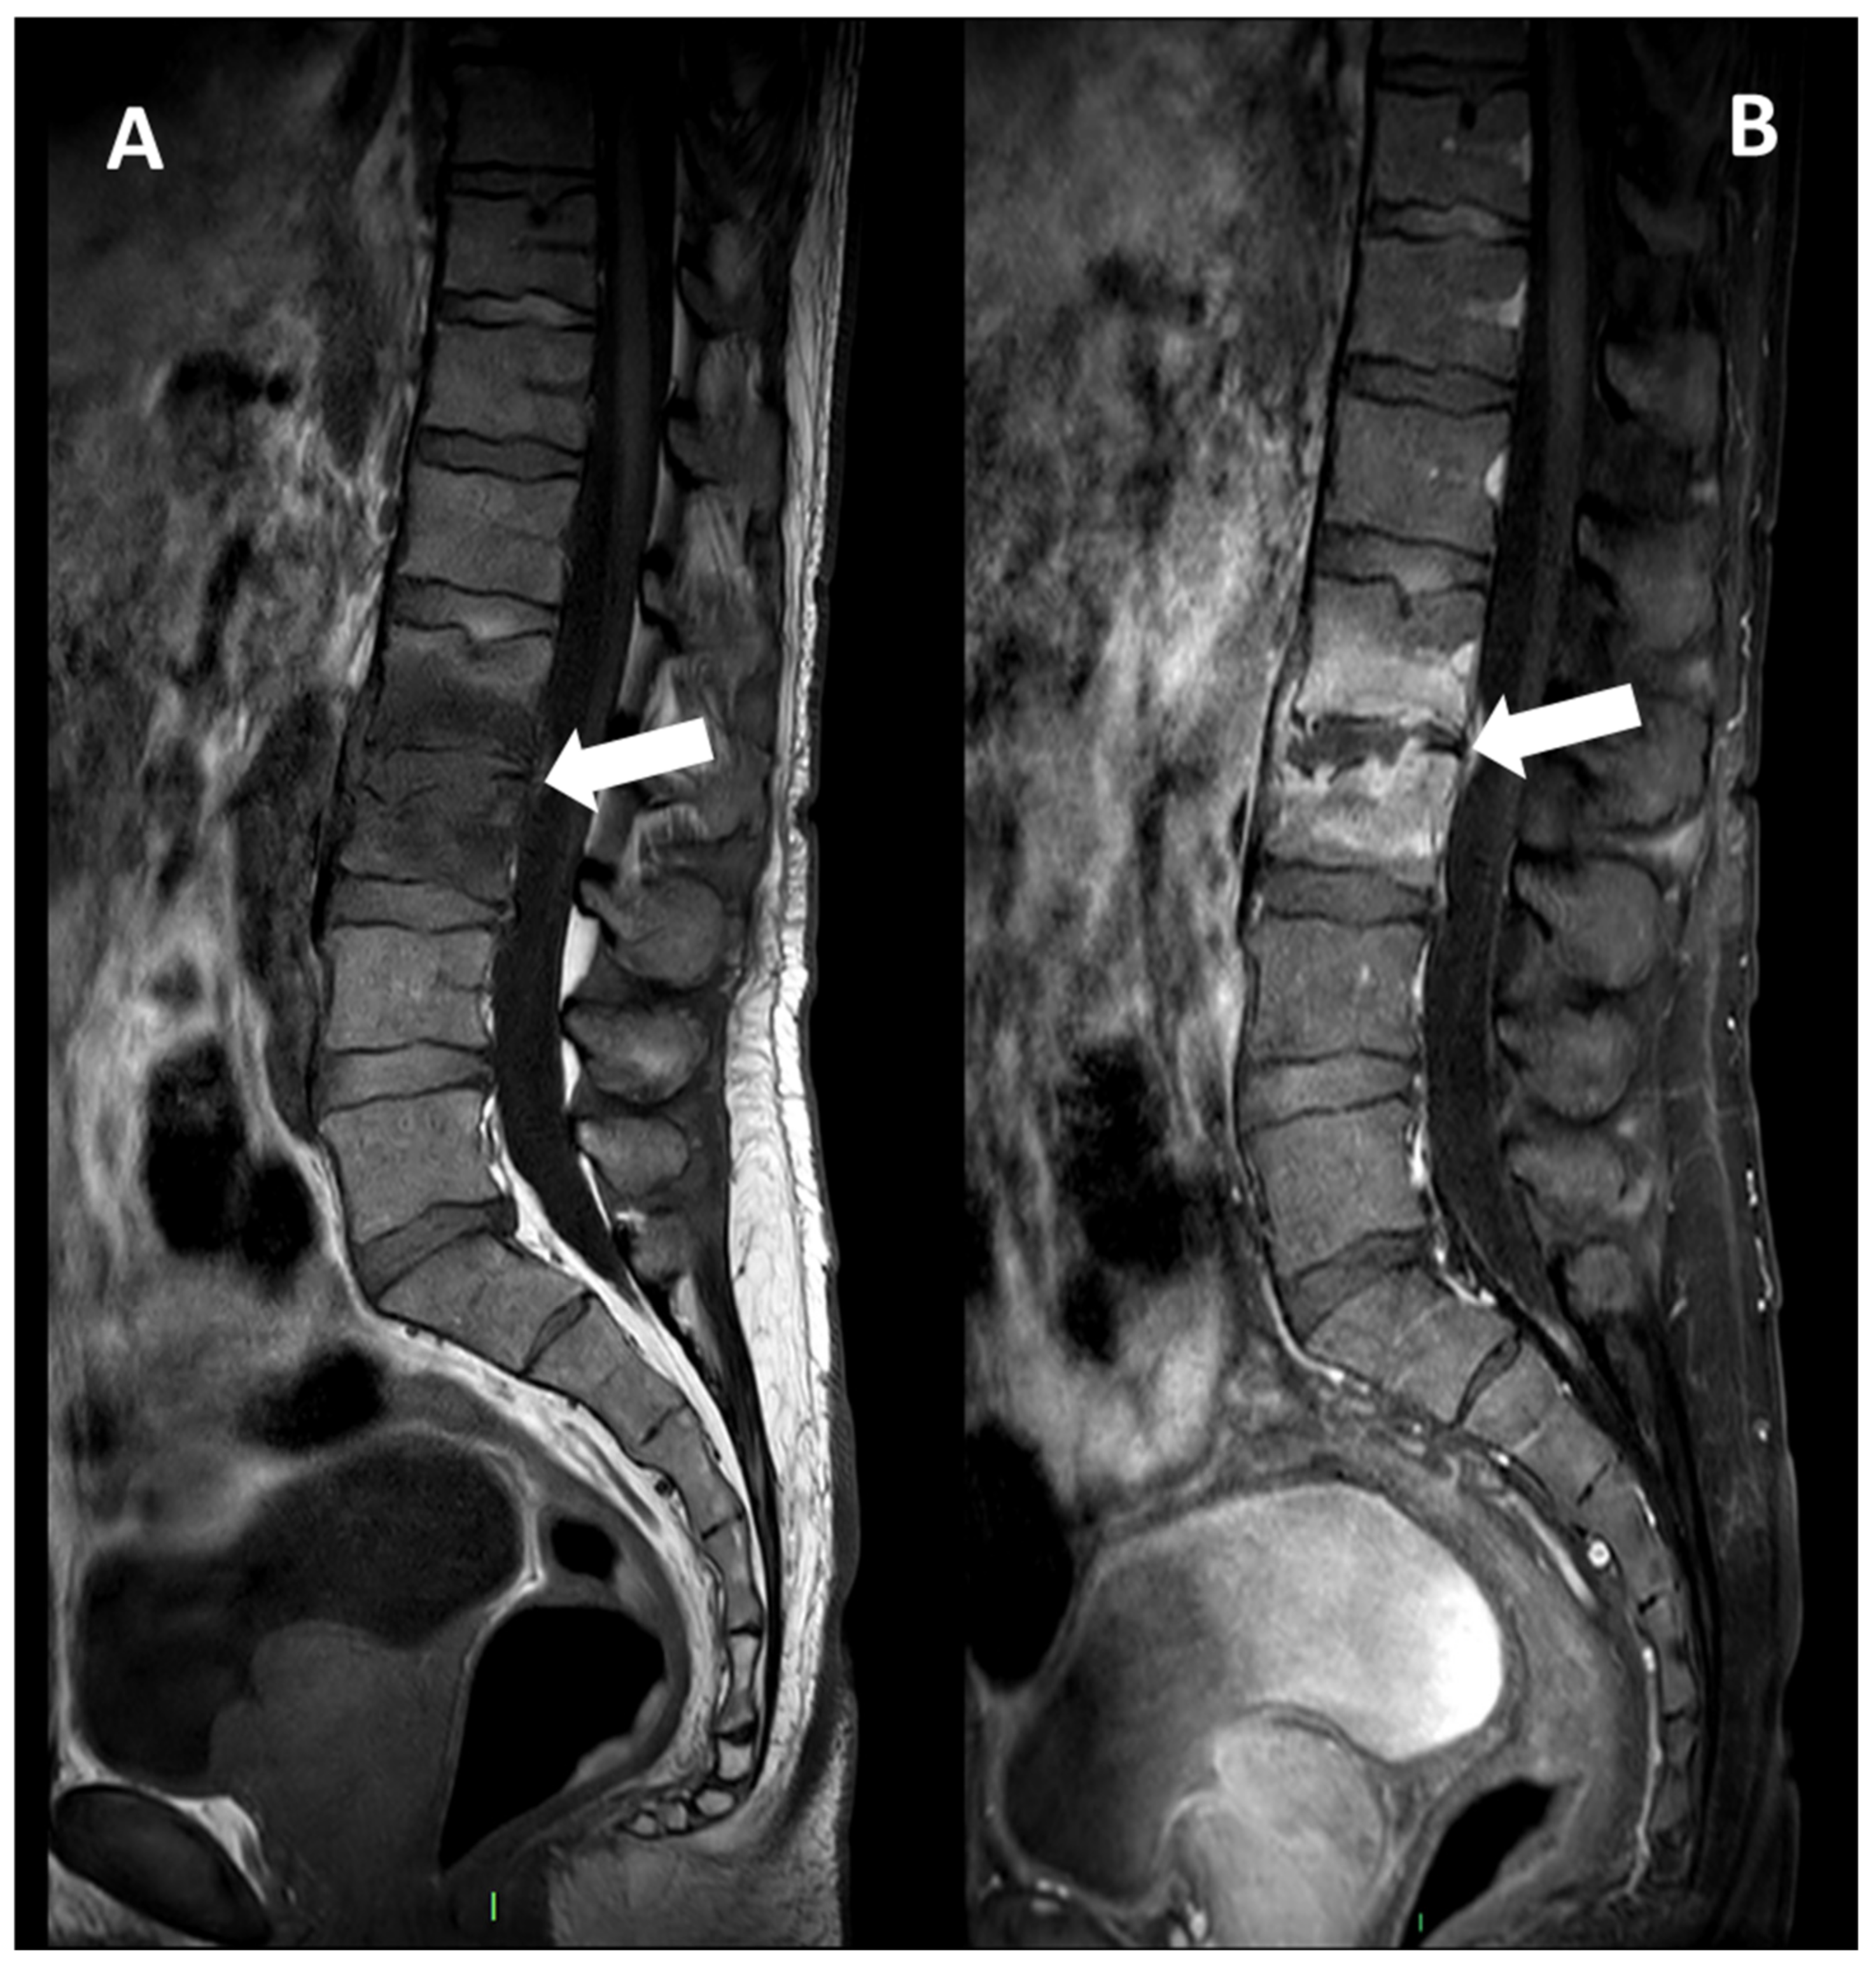

Figure 4. MRI, Sagittal T1w (Panel A), and T1w after contrast media injection (Panel B) of a 54-year-old male with pyogenic spondylodiscitis of L2-L3 vertebrae: complete alteration of disc signal intensity, endplates erosions, and diffuse pattern of vertebral body enhancement are detectable (arrows).

Spondylodiscitis induces inflammatory exudate that replaces normal marrow with white cells and causes hyperemia. This leads to changes in MRI signals, manifesting as hypo- or isointense T1 and hyperintense T2 signal intensities in the subchondral end plates and intervening disc. Typically, signal alterations initiate in the anterior aspect of the vertebral body, affecting single or multiple spinal segments. It can be unilateral at the early stage of the disease. Again, bone erosions of the endplates are observed. The contrast enhancement of the vertebral endplate can demonstrate various patterns, namely diffuse, patchy, clumped, or linear enhancement parallel to the endplate (Figure 4).